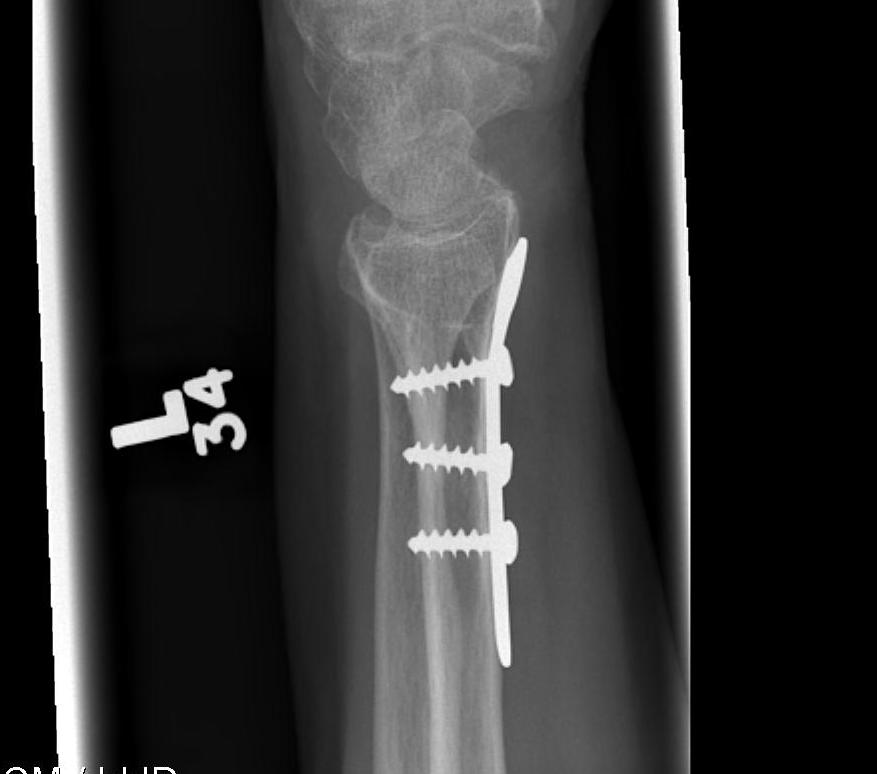

K wires

Volar locking plates

Distal Radius Fracture K wires APplateex fixbridge plate

Plates v External Fixation

Gou et al BMC Musculoskeletal 2021

- systematic review of external fixation versus volar locking plates

- 12 studies and 1200 patients

- better outcome scores and lower complications with volar locking plates